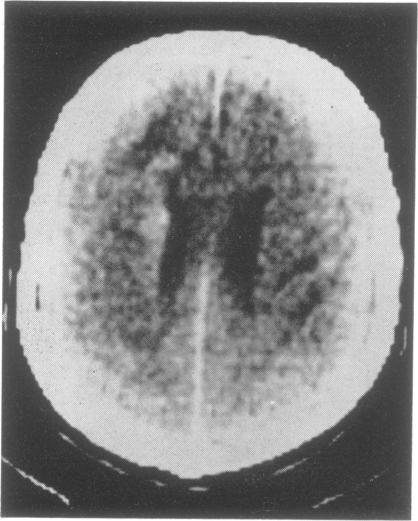

A case of cerebral mycosis fungoides co-existing with progressive multifocal leucoencephalopathy presented with dementia. Brain biopsy established the diagnosis of mycosis fungoides after cerebrospinal fluid examinations and computerised tomographic scanning of the brain produced non-specific abnormalities.

一例蕈样霉菌病合并进行性多灶性白质脑病的患者表现为痴呆。在脑脊液检查及脑部计算机断层扫描显示非特异性异常后,脑活检确诊为蕈样霉菌病。